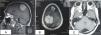

ProgressInvestigations revealed two extra-axial space-occupying lesions, one parasagittal at the right frontal and parietal lobes and the other located at the right temporal lobe pole. A surgical resection was planned for the parasagittal lesion and the histopathological diagnosis was meningeal melanocytosis. The temporal pole lesion was referred for treatment with Gamma Knife®.